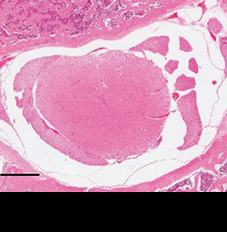

척추관 및 척수 형태 회복

척추관협착증을 유도한 쥐는 척추관이 좁아져 척수의 모양이 망가집니다.

여기에 신바로2를 투여하자 척추관과 척수의 형태가 정상에 가깝게 회복됐습니다.

정상 쥐

척추관협착증 유도 쥐

신바로2 약침 투여 쥐